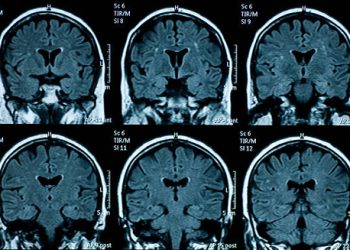

Diagnosis of Cluster Headaches Diagnosis of cluster headaches...